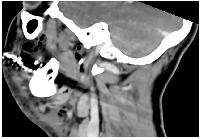

Figure 1: Sagittal CT imaging in cervicofacial necrotizing fasciitis.

Sagittal contrast-enhanced computed tomography (CT)

scan of the neck demonstrating hallmark features of cervicofacial necrotizing fasciitis, including subcutaneous emphysema, diffuse fascial

thickening, and fluid tracking along the deep cervical spaces. The sagittal plane highlights the craniocaudal spread of infection and illustrates

the rapid progression along anatomical compartments.